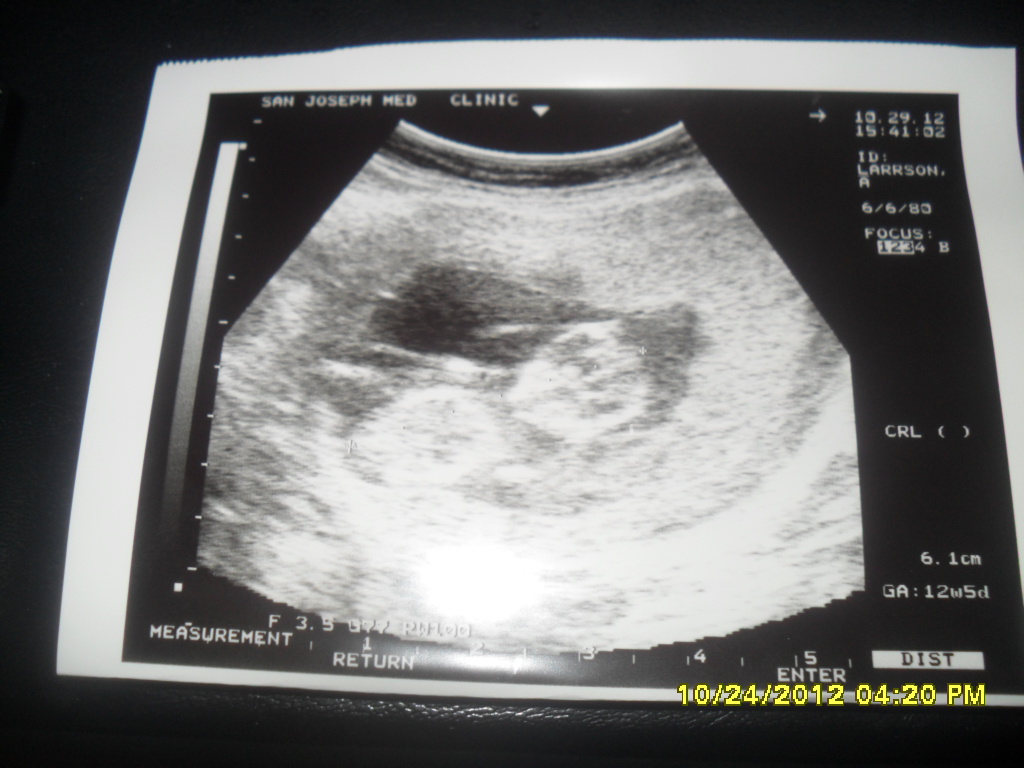

Such a horrible pic but if you could try to make out a guess it would be much appreciated! Cant see the nub area (Dr took the first image he saw) so Im thinking it looks like a Boy skull but again its really hard to tell and the quality is awful! :awe: was 169... Thank girls!!

Attachment 5773